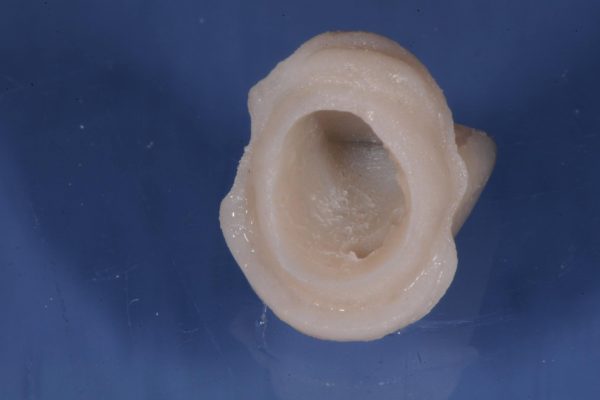

ottenere il massimo dell’estetica nella realizzazione di un manufatto protesico, è anche riuscire a dare forma e qualità ai tessuti che lo circondano.

La tecnica BOPT permette, attraverso un …